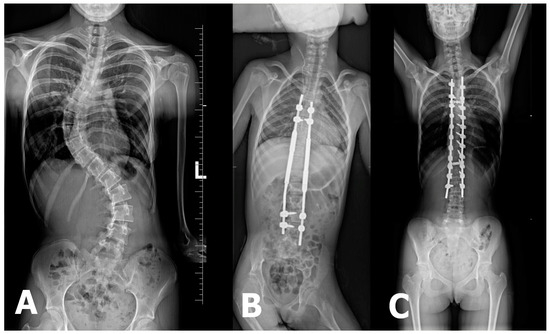

For early-onset scoliosis (EOS), occurring before the age of 10, growth-friendly surgical techniques such as magnetically controlled growing rods (MCGR) are frequently used to facilitate spinal and thoracic development while maintaining deformity correction. Traditional approaches, such as posterior spinal fusion (PSF), may lead to complications, including thoracic insufficiency syndrome, growth restriction, and respiratory issues, if performed too early. MCGR systems offer a promising alternative by reducing the need for repeated surgical lengthening procedures, thereby minimizing complications and psychosocial burden on young patients [21] (Figure 1).

Figure 1.

(A) X-ray image depicting severe double-curve scoliosis with Cobb angle measurements of 62° between L4/L5 and Th11/Th12 and 77° between Th11/Th12 and Th6/Th5. (B) X-ray image showing the magnetically controlled growing-rod (MCGR) system used for spinal stabilization. (C) X-ray image illustrating the final spinal stabilization procedure.